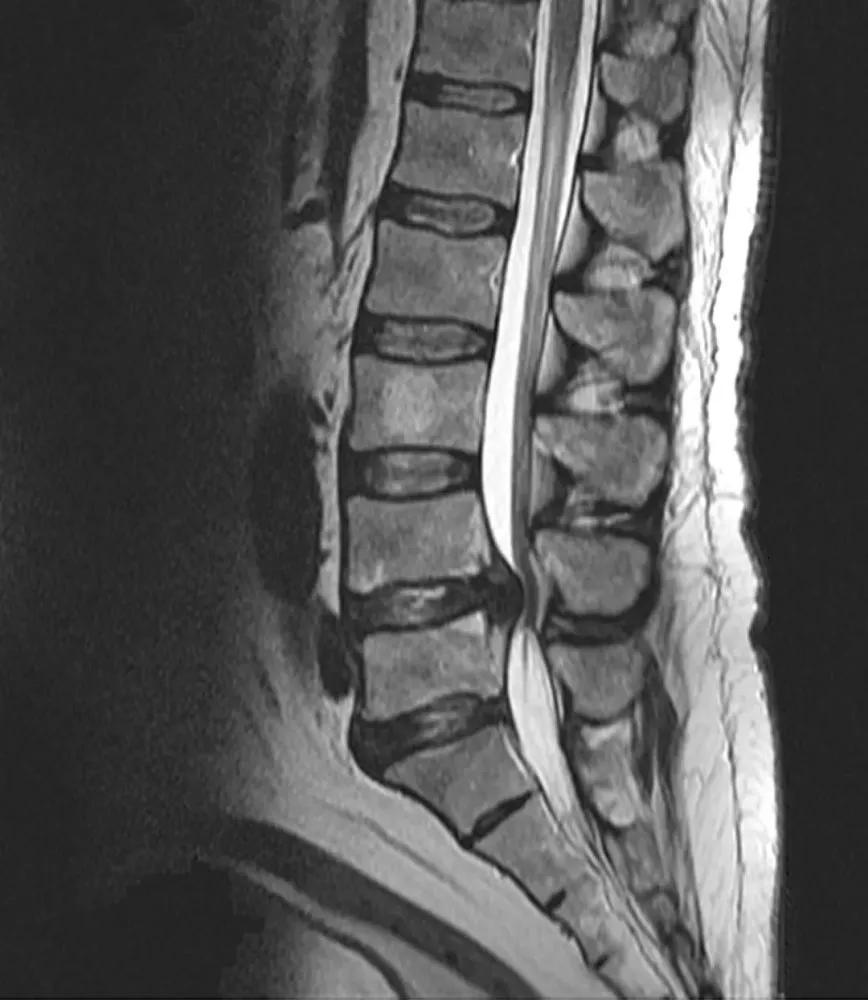

MRI检查

MRI , 即核磁共振检查 , 有良好的软组织分辨率 , 对骨关节内结构、骨髓及软组织病变的显示优于DR和CT , 但难以分辨骨软组织内较细小的钙化或骨化 , 骨皮质的显示也不如DR和CT 。 MRI扫描可以清晰观察病变椎间盘突出的部位、程度、形态及其与周围组织的关系 , 对神经根的压迫程度及是否出现椎间盘脱出、游离 , 对手术方案制定有重要意义 。

文章图片